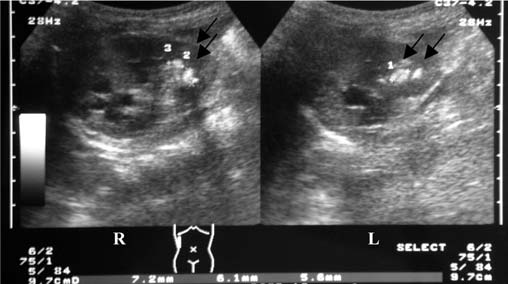

Choice ( B) - Renal Ultrasound is the correct answer. This phenomenon results from external compression of the kidney by a subcapsular hematoma. It is a rare, treatable cause of secondary hypertension mediated by activation of the renin-angiotensin-aldosterone system (RAAS) and hence the ideal agents for the treatment of hypertension are RAAS blockers.Page kidney induced by SWL is a rare complication with an incidence rated around 0.5%. . Conservative treatment should be considered in clinically stable patients with use of antihypertensive agents . However, surgical evacuation is usually required in the event of persistent hypertension, a very large hematoma or decreased renal function. The two main goals of intervention are renal decompression by the evacuation of the hematoma by open or percutaneous drainage of the compressing collection. If the collection has been long-standing, a fibrocollagenous shell may have formed, and this may require decapsulation of this shell or even nephrectomy. Percutaneous drainage has been observed to have better success rates in subcapsular hematomas that are of less than three weeks duration. External compression of the kidney may be due to a collection of blood from Blunt trauma, Iatrogenic - following biopsy of native or transplant kidney, extracorporeal shockwave lithotripsy, ureteral surgery, sympathetic nerve block or Spontaneous - anticoagulation, AV malformation, tumor, vasculitis, pancreatitis. Non-bleeding causes of external compression include lymphoceles particularly around the transplanted kidney, urinoma, retroperitoneal paraganglioma, or large simple cysts. ultrasound (US) was performed in this patient and it showed subcapsular hematoma of 15.5 mm thickness in the RK.